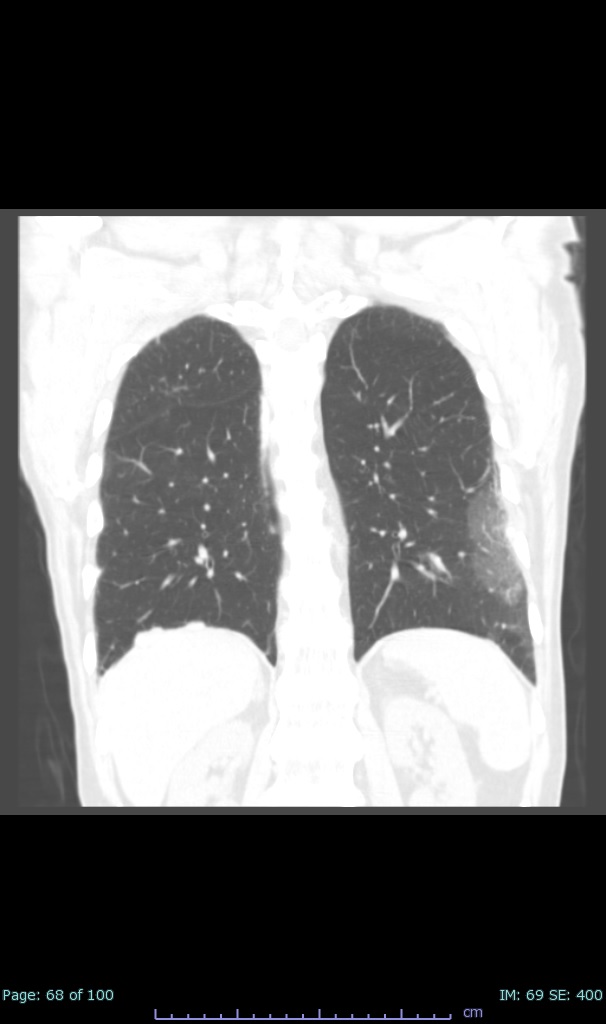

- 100% subpleural involvement, 33% + centrolobular involvement

- 40% even apical/basilar, 27% basilar dom, 5% mid dom. 1/17

I'll list age decade and + exposure documented #covid19 #coronavirus #radiology #FOAMed #radres 2/17